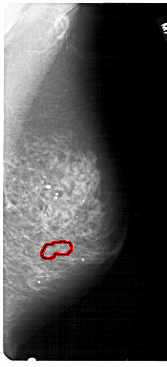

RIGHT_MLO LINES 5491 PIXELS_PER_LINE 2491 BITS_PER_PIXEL 12 RESOLUTION 43.5 OVERLAY

FILE: A_1831_1.RIGHT_MLO.OVERLAY

TOTAL_ABNORMALITIES 1

ABNORMALITY 1

LESION_TYPE CALCIFICATION TYPE PUNCTATE DISTRIBUTION CLUSTERED

ASSESSMENT 4

SUBTLETY 1

PATHOLOGY BENIGN

TOTAL_OUTLINES 1

BOUNDARY